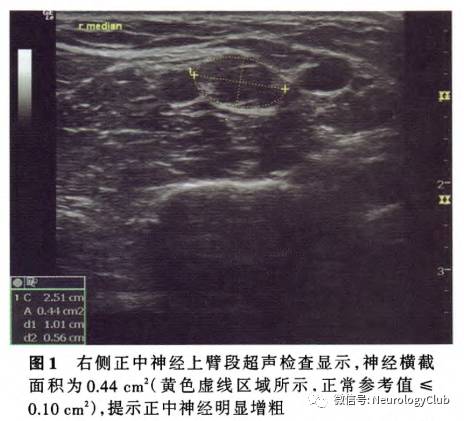

辅助检查 实验室检查血尿便常规、血清脂质、叶酸、红细胞沉降率(ESR)、甲状腺功能试验、凝血功能试验和感染四项均于正常值范围;空腹血糖水平12.20 mmol/L(3.90-6.10mmol/L),糖化血红蛋白7.60%,血清尿酸454μmol/L(210-416μmol/L),维生素B12(服用甲钴胺后)777pmol/L(80-675pmol/L);抗核抗体(ANA)谱(18项)、抗可提取性核抗原(ENA)抗体、抗中性粒细胞胞质抗体(ANCA)谱均于正常值范围,血清免疫固定电泳(IFE)阴性;血清肿瘤标志物筛查阴性。腰椎穿刺脑脊液外观清亮、透明,压力120mmH2O(1mmH2O=9.81*10-3kPa,80-180mmH2O),常规于正常值范围,蛋白定量1070mg/L(150-450mg/L)、葡萄糖水平6.50mmol/L(2.50-4.50mmol/L)、氯化物于正常值范围,墨汁染色、抗酸染色、真菌涂片、细菌涂片和隐球菌抗原均呈阴性,髓鞘碱性蛋白(MBP)于正常值范围,脑脊液IgG 101mg/L(10-40mg/L),寡克隆区带阳性、特异性寡克隆区带阳性;血清IgG于正常值范围,寡克隆区带阴性。血清和脑脊液免疫荧光染色6项中抗Hu、Ri、Yo抗体,抗CV2/CRMP5抗体,抗PNMA2(Ma2/Ta)抗体,抗两性蛋白(amphiphysin)抗体均呈阴性;血清和脑脊液抗莱姆病螺旋体抗体(IgG)、抗神经节苷脂抗体GM1(IgG+IgM)均呈阴性。影像学检查:肝、胆、胰、脾超声显示,胆囊壁毛糙,胆囊结石;双肾、输尿管、膀胱、前列腺超声显示前列腺稍增大;双侧正中神经和尺神经超声显示,神经横截面积(CSA)明显增大,提示神经增粗(图1);双侧颈动脉、椎动脉和锁骨下动脉(SCA)彩色多普勒超声(CDUS)及胸部X线均未见明显异常。神经电生理学检查:节段性运动神经传导未见传导阻滞(运动神经传导波幅降低,远端潜伏期延长,双侧桡神经运动传导速度减慢);神经传导速度提示四肢周围神经源性损害,包括感觉纤维和运动纤维(运动神经传导速度<38m/s);肌电图提示四肢肌肉和T10椎旁竖脊肌神经源性损害;四肢交感皮肤反应(SSR)未见明显异常。基因检测显示,周围髓鞘蛋白22(PMP22)外显子1_5重复突变(EXl_5 DUP),为杂合子。

神经电生理学检查、神经超声检查和基因检测对明确诊断遗传性运动感觉神经病至关重要。针极肌电图呈现神经源性损害;神经传导速度有助于区分脱髓鞘改变和轴索损害,传统遗传性运动感觉神经病的临床分型基于病理学检查、基因检测和神经电生理学检查(正中神经运动神经传导速度≥38m/s为轴索损害,<38m/s为脱髓鞘改变),该例患者正中神经运动神经传导速度<38m/s,故属CMTl型。神经超声是近年新兴的周围神经病变诊断技术,目前逐渐应用于临床。遗传性运动感觉神经病(CMT1型),特别是CMT1A基因型神经超声可见神经横截面积增大,提示弥漫性神经增粗,是反复脱髓鞘改变导致施万细胞和神经间质增生的结果而慢性炎性脱髓鞘性多发性神经根神经病神经超声显示多灶性块状神经增粗。该例患者双侧正中神经和尺神经超声符合典型脱髓鞘改变表现,支持遗传性运动感觉神经病(CMT1型)的诊断。随着分子生物学的发展,继1991年发现首个致病基因PMP22(17p11.2-12串联重复)以来,相继有60余种致病基因或致病相关基因见诸报道(表1)。该例患者家族史可疑阳性,基因检测显示PMP22基因杂合突变,CMT1A基因型诊断明确;PMP22基因负责编码周围髓鞘蛋白,该蛋白为周围神经髓鞘重要成分,PMP22基因突变致周围髓鞘蛋白拷贝数变异可以造成周围神经髓鞘结构异常,可能是周围神经病变的发病机制。患者父亲和胞姊可疑四肢远端肌萎缩、肢体纤细,考虑为家族遗传,建议患者直系亲属必要时行相关基因检测以评估发病风险。基于近年二代测序技术的广泛应用和遗传性运动感觉神经病基因型的异质性特点,基因型与临床表型之间存在复杂关联性的观点逐渐被认可,传统遗传性运动感觉神经病分类已不能全面反映对疾病本质的认识,Mathis等建议采用新的遗传性运动感觉神经病分类标准,根据遗传学表现、临床特点和致病基因命名和分类,如AD-CMTde-PMP22dup或AD-AMTax-MFN2,其中包含68种变异型,共计54种已知致病基因和3种未知基因;鉴于其对相关指标和实验室检查要求较高,目前尚未在临床广泛应用,其可行性尚待进一步研究加以验证。